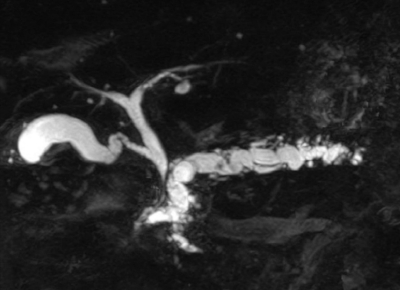

血液生化学所見:総ビリルビン 1.0 mg/dL、AST 84 U/L、ALT 53 U/L、ALP 258 U/L(基準 115〜359)、γ-GTP 110 U/L (基準8〜50)、アミラーゼ 215 U/L (基準 37〜160)、空腹時血糖 278 mg/dL、HbA1c 9.6 %(基準 4.6〜6.2)、CA19-9 32 U/mL (基準 37 以下)。腹部CTとMRCPとを示す。